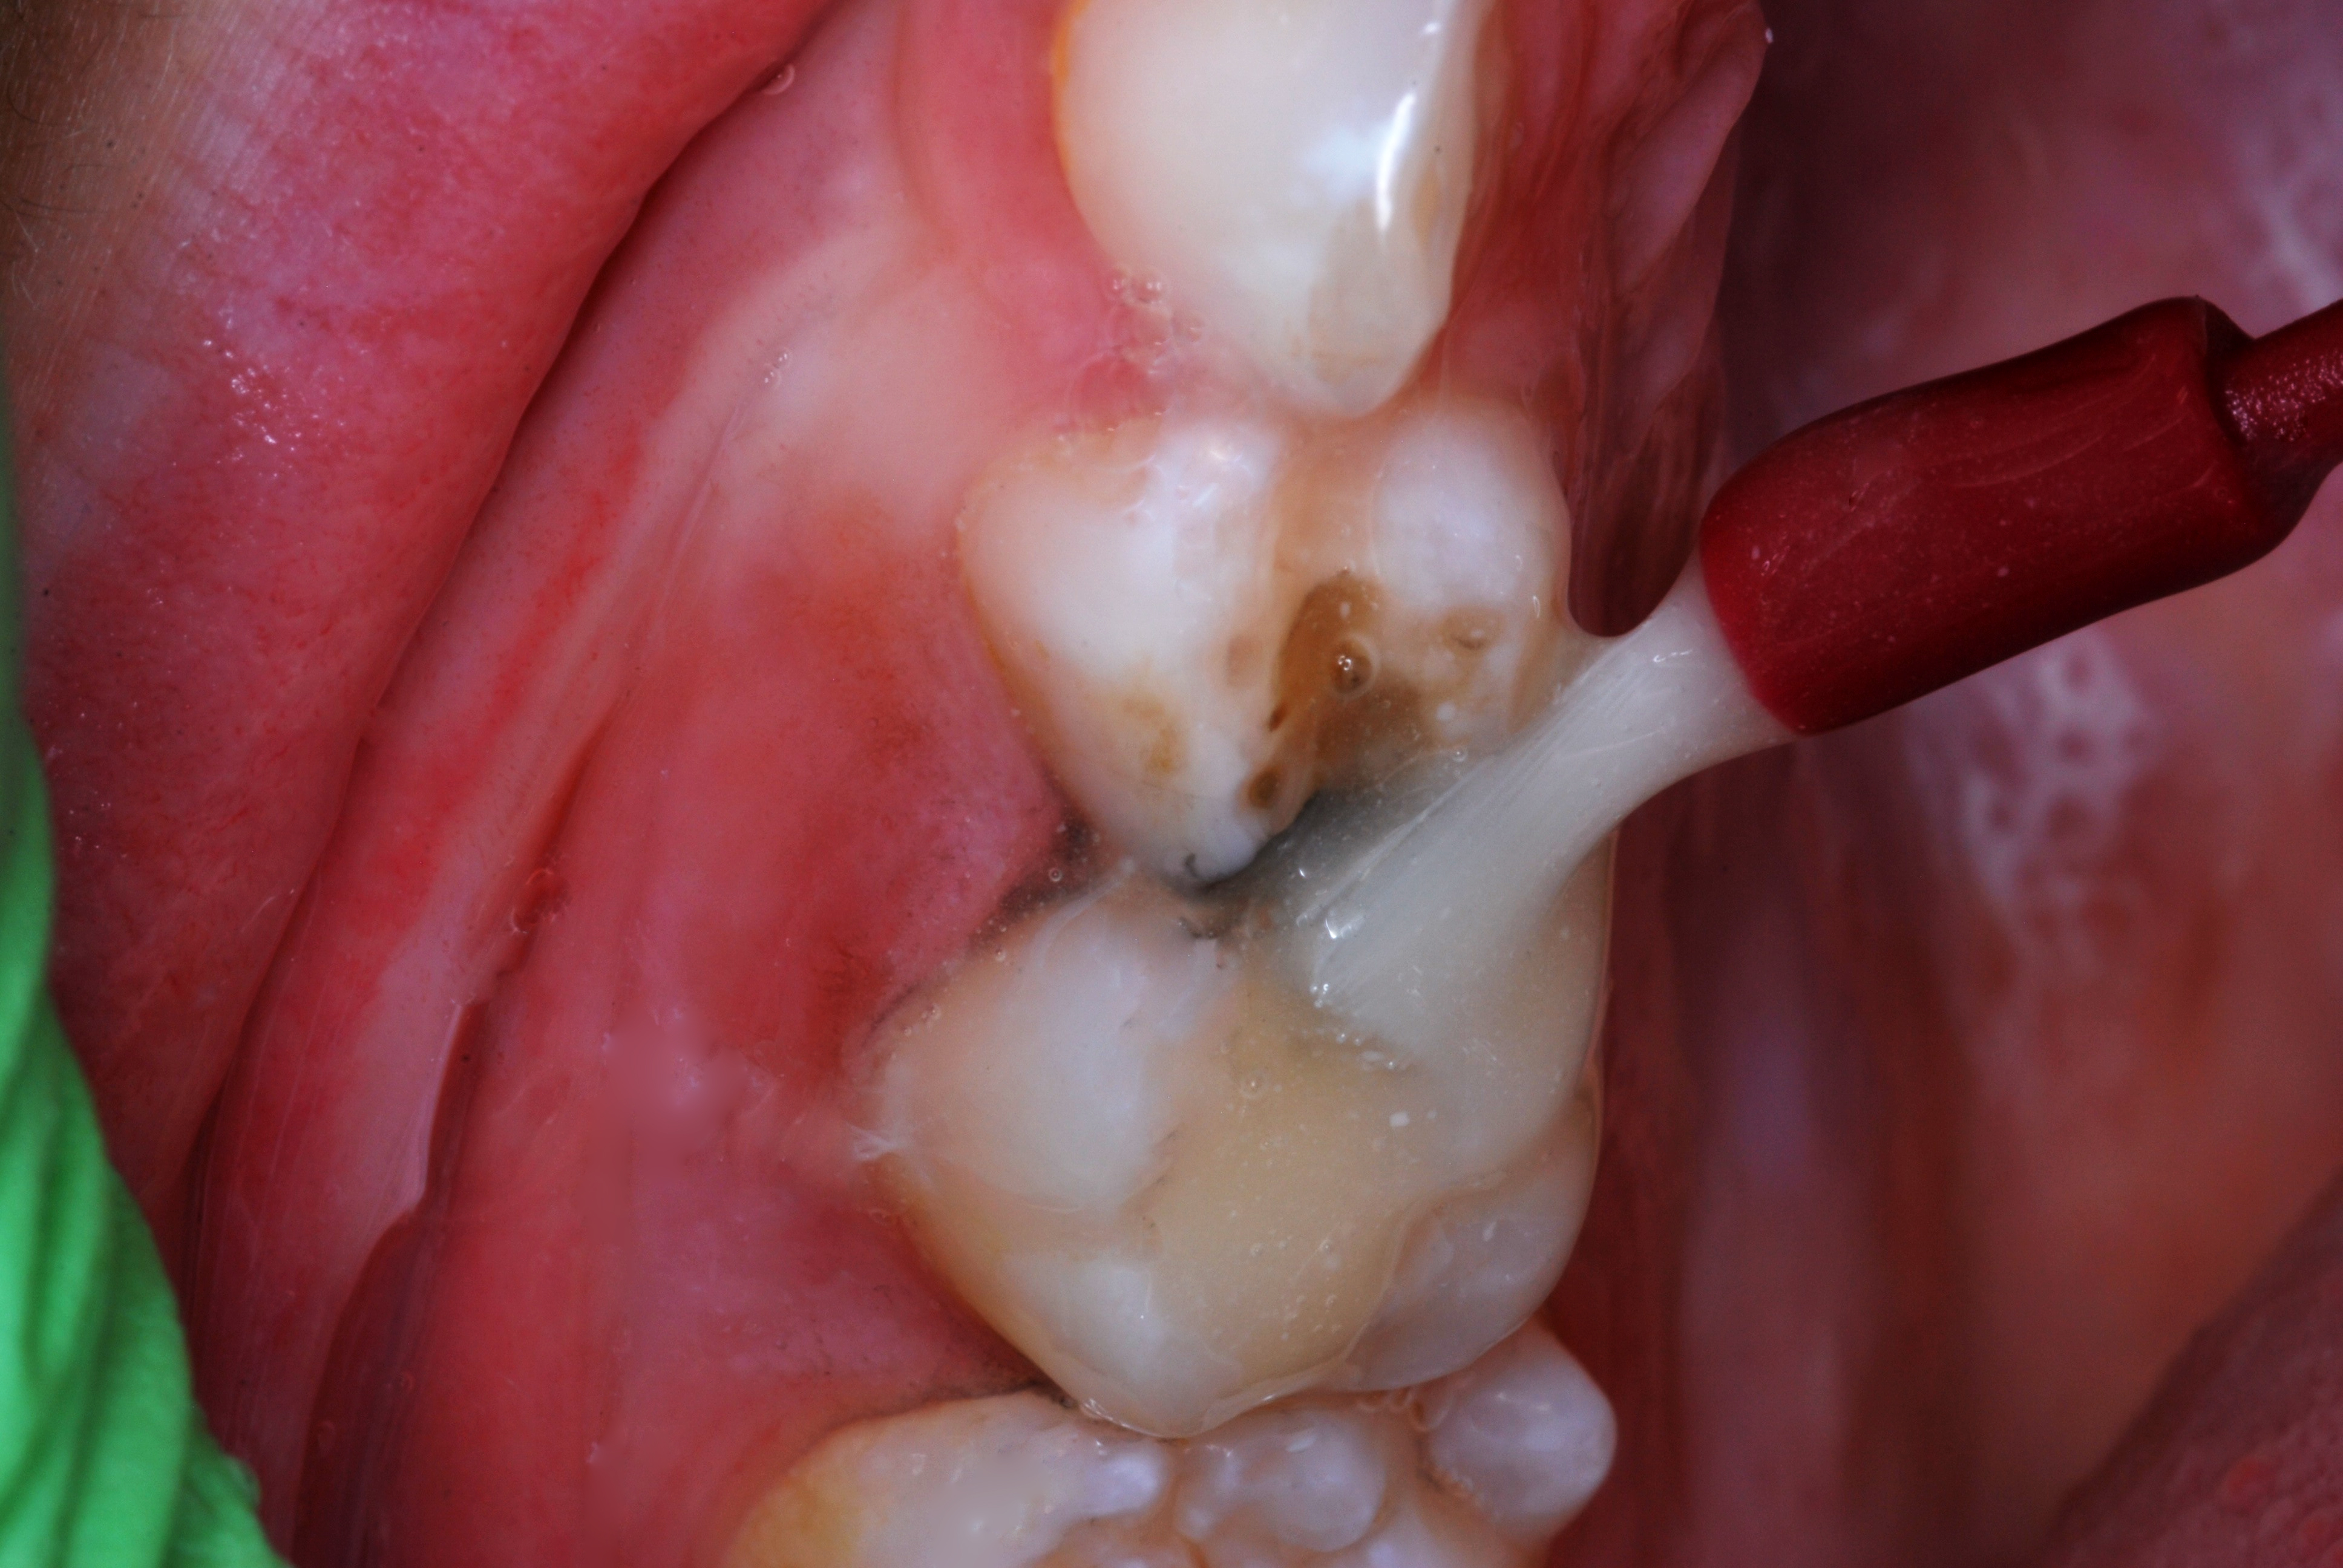

(4.) SDF treated molar in a 3-year-old patient, 4 months after application.

Figure 4

(5.) Second application of SDF being applied at 4-month follow-up appointment.

Figure 5